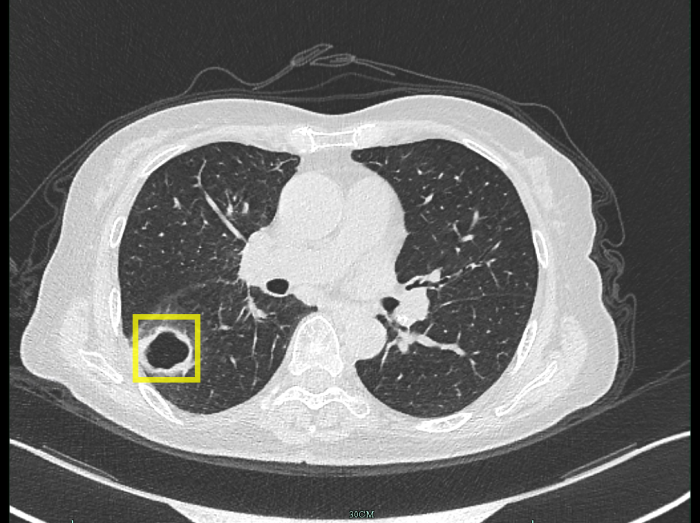

柴阿姨最開始以為只是普通感冒,自行吃藥后并沒有好轉(zhuǎn)。感到焦慮的柴阿姨便到當?shù)蒯t(yī)院就診,經(jīng)肺部CT檢查發(fā)現(xiàn),肺部出現(xiàn)空洞病灶。

空洞病灶

迷團終于解開,原來引起柴阿姨肺部空洞的“罪魁禍首”不是肺結(jié)核,而是真菌感染。

此后,經(jīng)過抗真菌治療,柴阿姨肺部的空洞已經(jīng)愈合消失。